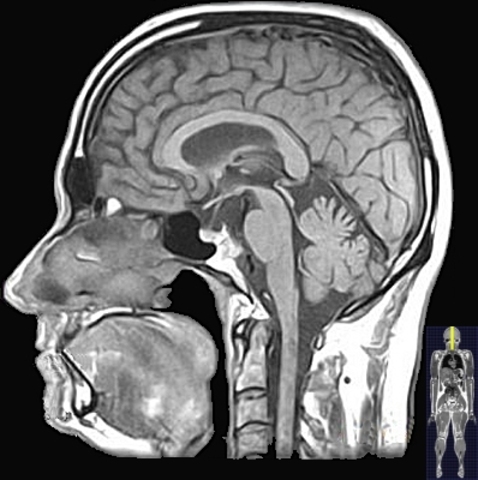

• MRI: escaneo por resonancia magnética

MRI: escaneo por resonancia magnética

MRI Hasta 1974 los usos de los principios físico-químicos de la resonancia magnética (MR) fueron unidimensionales y sin producir información espacial. P. C. Lauterbur (químico) y P. Mansfield (físico) independientemente lograron ese año su aplicación para el escaneo de imágenes bidimensionales que indican el origen y posición relativa de la fuente de señal: MRI. Esta tecnología es ahora indispensable en el diagnóstico médico.